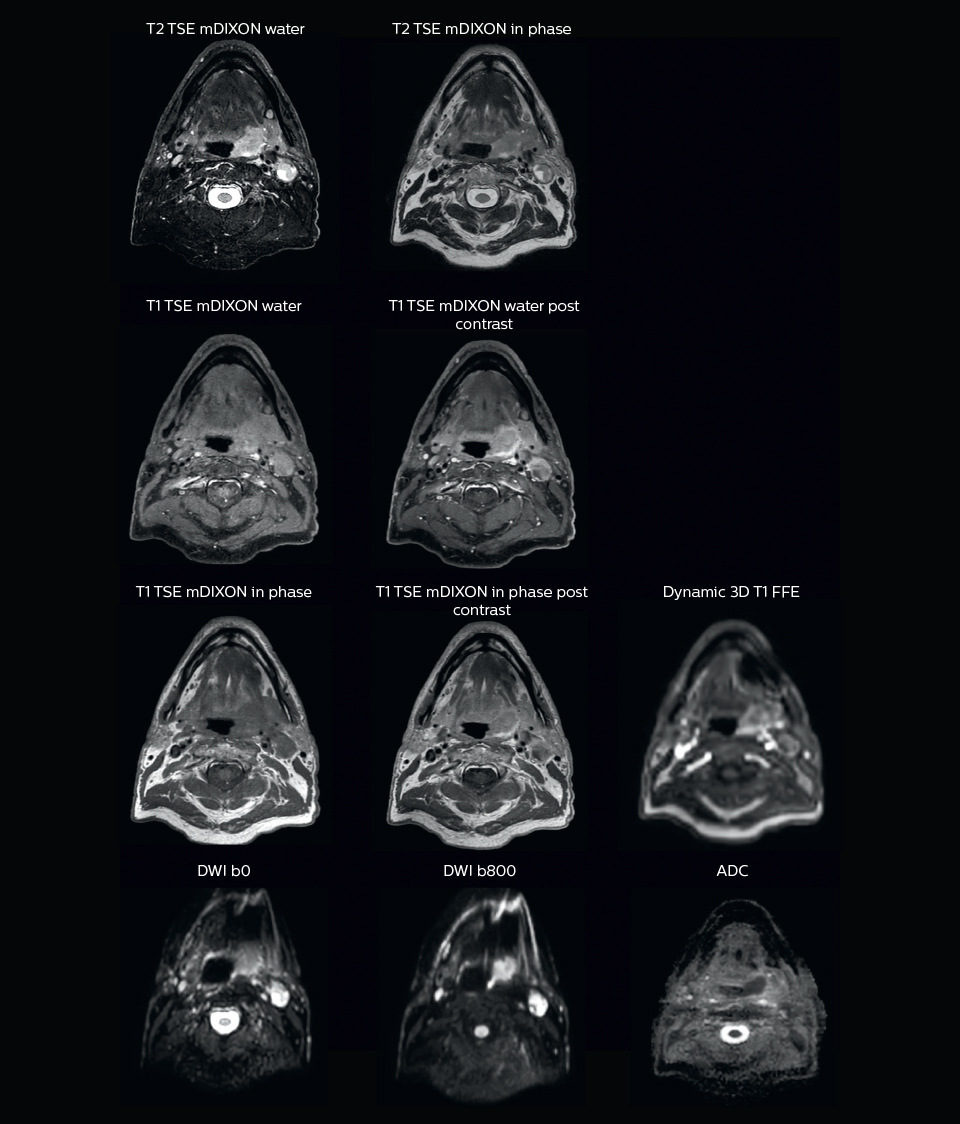

“We use pre- and post-contrast T1- and T2-weighted sequences with the fast and robust mDIXON method for fat suppression,” says Dr. Philippens. “Dynamic contrast-enhanced imaging is performed with high temporal resolution and low spatial resolution, to see the contrast agent uptake in the tumor. Diffusion weighted imaging is used qualitatively to see how the tumor extends into another structure, rather than for strict delineation.”

“When we can visualize intraprostatic lesions, the radiation therapist can then plan to boost them, giving a higher dose to those lesions instead of giving a uniform dose to the whole prostate, in the hope to better treat the patient and have less risk of recurrent tumors. However, this is not yet clinical routine. For visualizing the lesions, we not only use anatomical, T2-weighted imaging, but also diffusion weighted MRI and dynamic contrast- enhanced MRI."